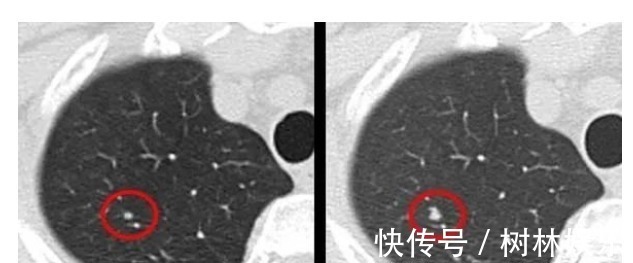

肺结节(肺部横截面)一般年龄大、肺部有基础疾病的人,做检查易发现肺部结节。只有极少部分人最后被证实是肺癌。检查方式:对于小于5毫米的微小结节,定期观察,3个月到半年重新做一次CT检查,但1厘米以上的大结节,建议要尽早诊治。★医生建议:40岁以上的人建议做一次低剂量螺旋CT,作为筛查可以发现一些早期肺结节。(关爱父母,陪他们做一次)★就诊科室:呼吸内科、肺结节诊治分中心。息肉:部分会恶变息肉就是身体某些部位多长了一块肉。